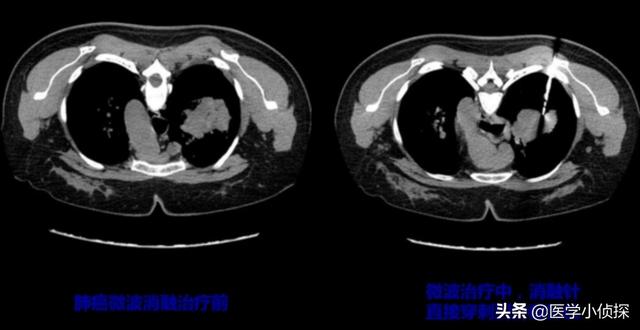

一種類骨転移のみ肋骨や椎骨の転移のような局所的な低侵襲治療でも、マイクロ波焼灼針を使用することで、十分な効果が得られます。

もう1つのケースは、広範で大規模な移籍という点でより問題である。この時、単一のアブレーション治療では、その効果に役割を果たすことが難しく、複数の場所に痛みがある場合、鎮痛剤を局所的に使用するだけでは、その効果は限定的であるため、骨の破壊を抑制する薬剤を使用するなどの統合的な治療を行う必要があります。同時に、肺がんをターゲットにすることも非常に重要であり、問題の根本的な原因の治療のために化学療法、標的薬などを含む使用は、もちろん、骨を行うために使用する可能性もあります。もちろん、骨を補強することによって局所の痛みを軽減することができる骨セメント補強治療の可能性もあります。しかし、結局のところ、根本的な原因を治療することに変わりはなく、それは肺がんを治すことなのです!